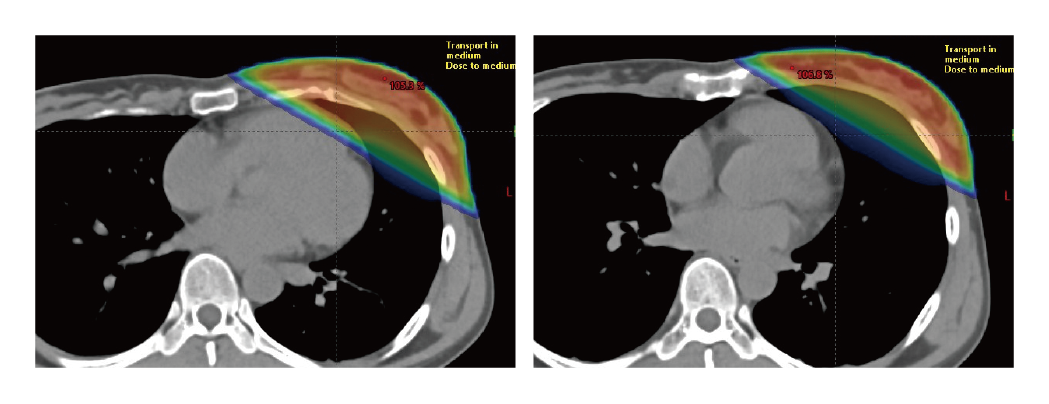

DIBH(深吸気息止め)

左乳がんへの放射線治療において、心臓への放射線被ばくを減らし心臓障害のリスクを下げる方法。当院では昨年から、左乳がんの乳房温存術後照射に導入しています。大きく息を吸うことで肺をふくらませ、心臓と患部が十分に離れた状態を維持している間に照射します。

高精度放射線治療では、照射位置を正確に決める必要があります。このため、毎回の治療時に画像を撮影して位置を正確に合わせ込む「画像誘導放射線治療」を行います。また、呼吸で動く部位には、所定の位置に患部が収まる時だけ照射する「呼吸同期照射」により精巧な治療を実現しています。左乳がんの術後照射では、深吸気息止め(DIBH)により心臓への照射を避けることができます。